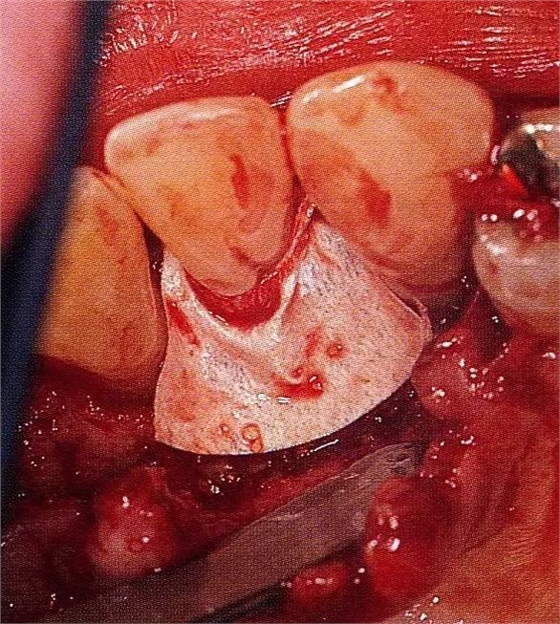

▲圖8-4,5為了確保足夠空間實(shí)現(xiàn)更好的再生,使用了2張鈦強(qiáng)化型gore-tex膜。

▲圖8-6通常,會(huì)將覆膜通過縫合線固定在牙齒上,但是,此情況下,使用了鑷子將覆膜進(jìn)一步往根尖側(cè)固定。